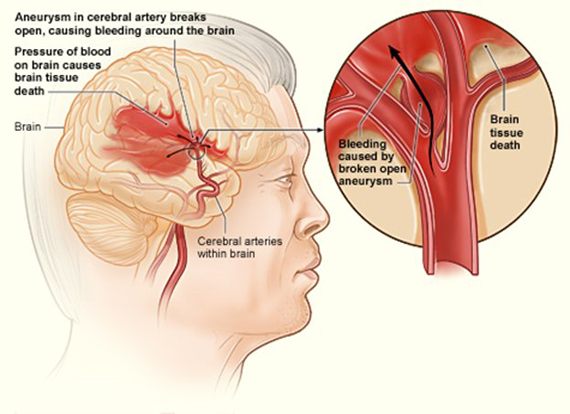

– A stroke

– Brain death

– Cerebral infarction and Cerebral hemorrhage